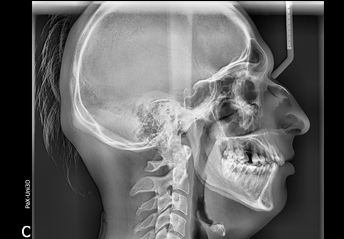

Tele-radiografía de frente y de perfil.

Trazados cefalométricos.